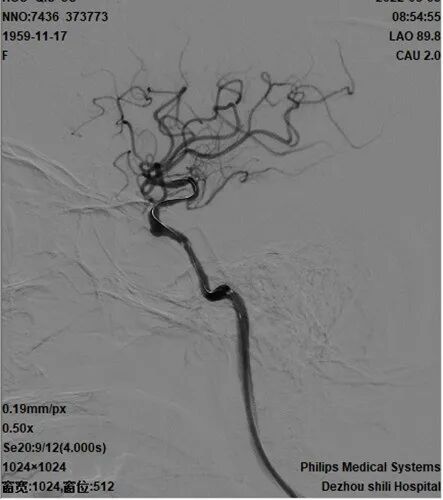

术后影像及检查

术后造影。

导丝怎么扩【载药时代 球扩天下】NOVA DES®颅内药物洗脱支架在颈内动脉颅内段重度狭窄的应用二例!_https://www.jmylbn.com_新闻资讯_第33张

手术总结

术中微导丝远端放置在大脑中动脉M1段,小心通过狭窄,避免栓子脱落及夹层出现。赛诺神畅 NOVA DES®内药物洗脱支架可视性及成型完美,期待能降低支架内再狭窄的发生。